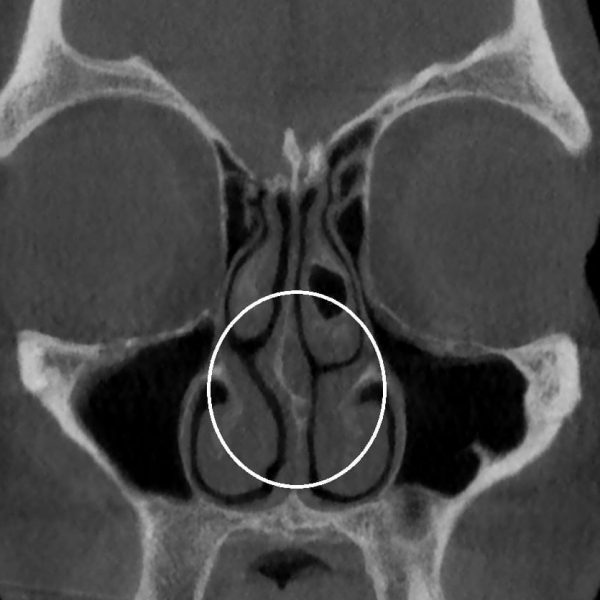

Desviación de tabique nasal

El diagnóstico se realiza mediante la exploración física nasal, a través de una rinoscopia anterior y en casos necesarios utilizando la endoscopia nasal. Con esto podemos ver la forma del septum cartilaginoso y óseo en toda su extensión.